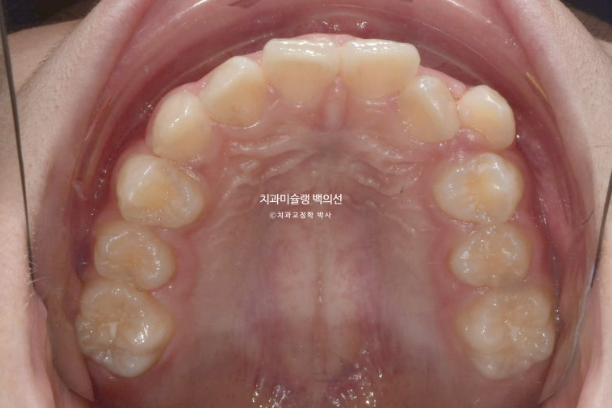

치료시작 1년째 모습입니다.

24.02

상악 발치공간은 편측으로 약 1/3 남아있으며 아직 한쪽 제2대구치가 나오지 않은 상황입니다.

두번째 큰어금니가 나오길 기다리며 치료를 천천히 이어갑니다.

교정 종료 시점에 뺏다꼈다 하는 유지장치를 제작해야 하는데

두번째 큰어금니까지 다 나온 후 제작하는 게 가장 좋기 때문입니다.

그래서 치료 종료 시기를 두 번째 큰어금니까지 나온 후로 연기하는 것이 좋습니다.

치료시작 2년 3개월차, 드디어 치료를 마무리 합니다.

25.05

중심선은 잘 맞으며 교합은 깔끔합니다.